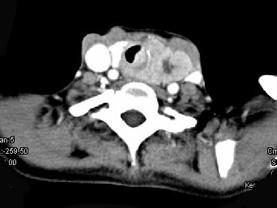

问题 女,50岁,左下颈部扪及一质硬、表面高低不平的包块,约半年,肿块逐渐增大,现感吞咽困难。如图所示CT诊断为()

选项 A.甲状腺癌 B.食管癌 C.喉癌 D.甲状腺原发淋巴瘤 E.颈部神经鞘瘤

答案 A